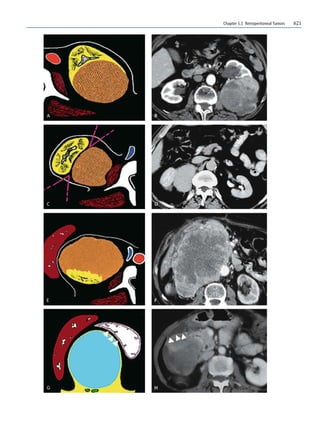

Fig. 1A–H. Origin of the mass. Positive beak sign: diagram (A) and

CT scan after CM administration (B).The appearance is supported

by parenchymal tokens that “envelop” the tumor. The lesion origi-

nates from the organ (renal mass).Negative beak sign: diagram (C)

and CT scan after contrast medium administration (D).The tumor

does not originate from the organ, which is also compressed. An

acute angle forms at the contact points between the resident organ

and the lesion as shown in (c) (retroperitoneal mass).E, F Phantom

organ sign: diagram (E) and CT scan after CM administration (F).

The tumor’s originating organ (right kidney) appears totally in-

corporated by the tumor and is no longer recognizable (F). Nega-

tive embedded organ sign: diagram (G) and CT scan after CM ad-

ministration (H).The wall of a hollow viscus is compressed extrin-

sically from the tumor creating a crescent shape (arrowheads)

쐌 The beak sign (positive when the mass causes the

edge of an adjacent organ to become beak shaped,

meaning that the mass arises from that organ)

(Fig. 1A–D).

쐌 The phantom organ sign (positive when a huge mass

arises from a small organ that then becomes unde-

tectable) (Fig. 1E, F).

쐌 The embedded organ sign (positive when part of a

hollow organ appears embedded in the tumor)

(Fig. 1G, H).